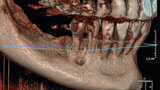

Fig. 13: CBCT reconstruction of a deficient ridge in the lateral mandible.

Fig. 14: Preoperative intraoral finding in the atrophic posterior mandible.